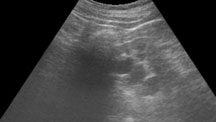

Ultraschallbild einer Nierenzyste Computertomografie einer Nierenzyste

Ultraschallbild einer Nierenzyste

Die Abklärung umfasst neben dem Ultraschall oft auch eine Bildgebung mit Computertomografie (CT) oder Magnetresonanztomografie (MRT).

Neben einer körperlichen Untersuchung, sowie Blut- und Urinprobe werden Nierenzysten zuerst mit dem Ultraschall untersucht und beurteilt. Manchmal muss zusätzlich eine Computertomografie oder Magnetresonanztomografie durchgeführt werden, um entscheiden zu können ob es sich wirklich um eine «harmlose» Nierenzyste handelt.